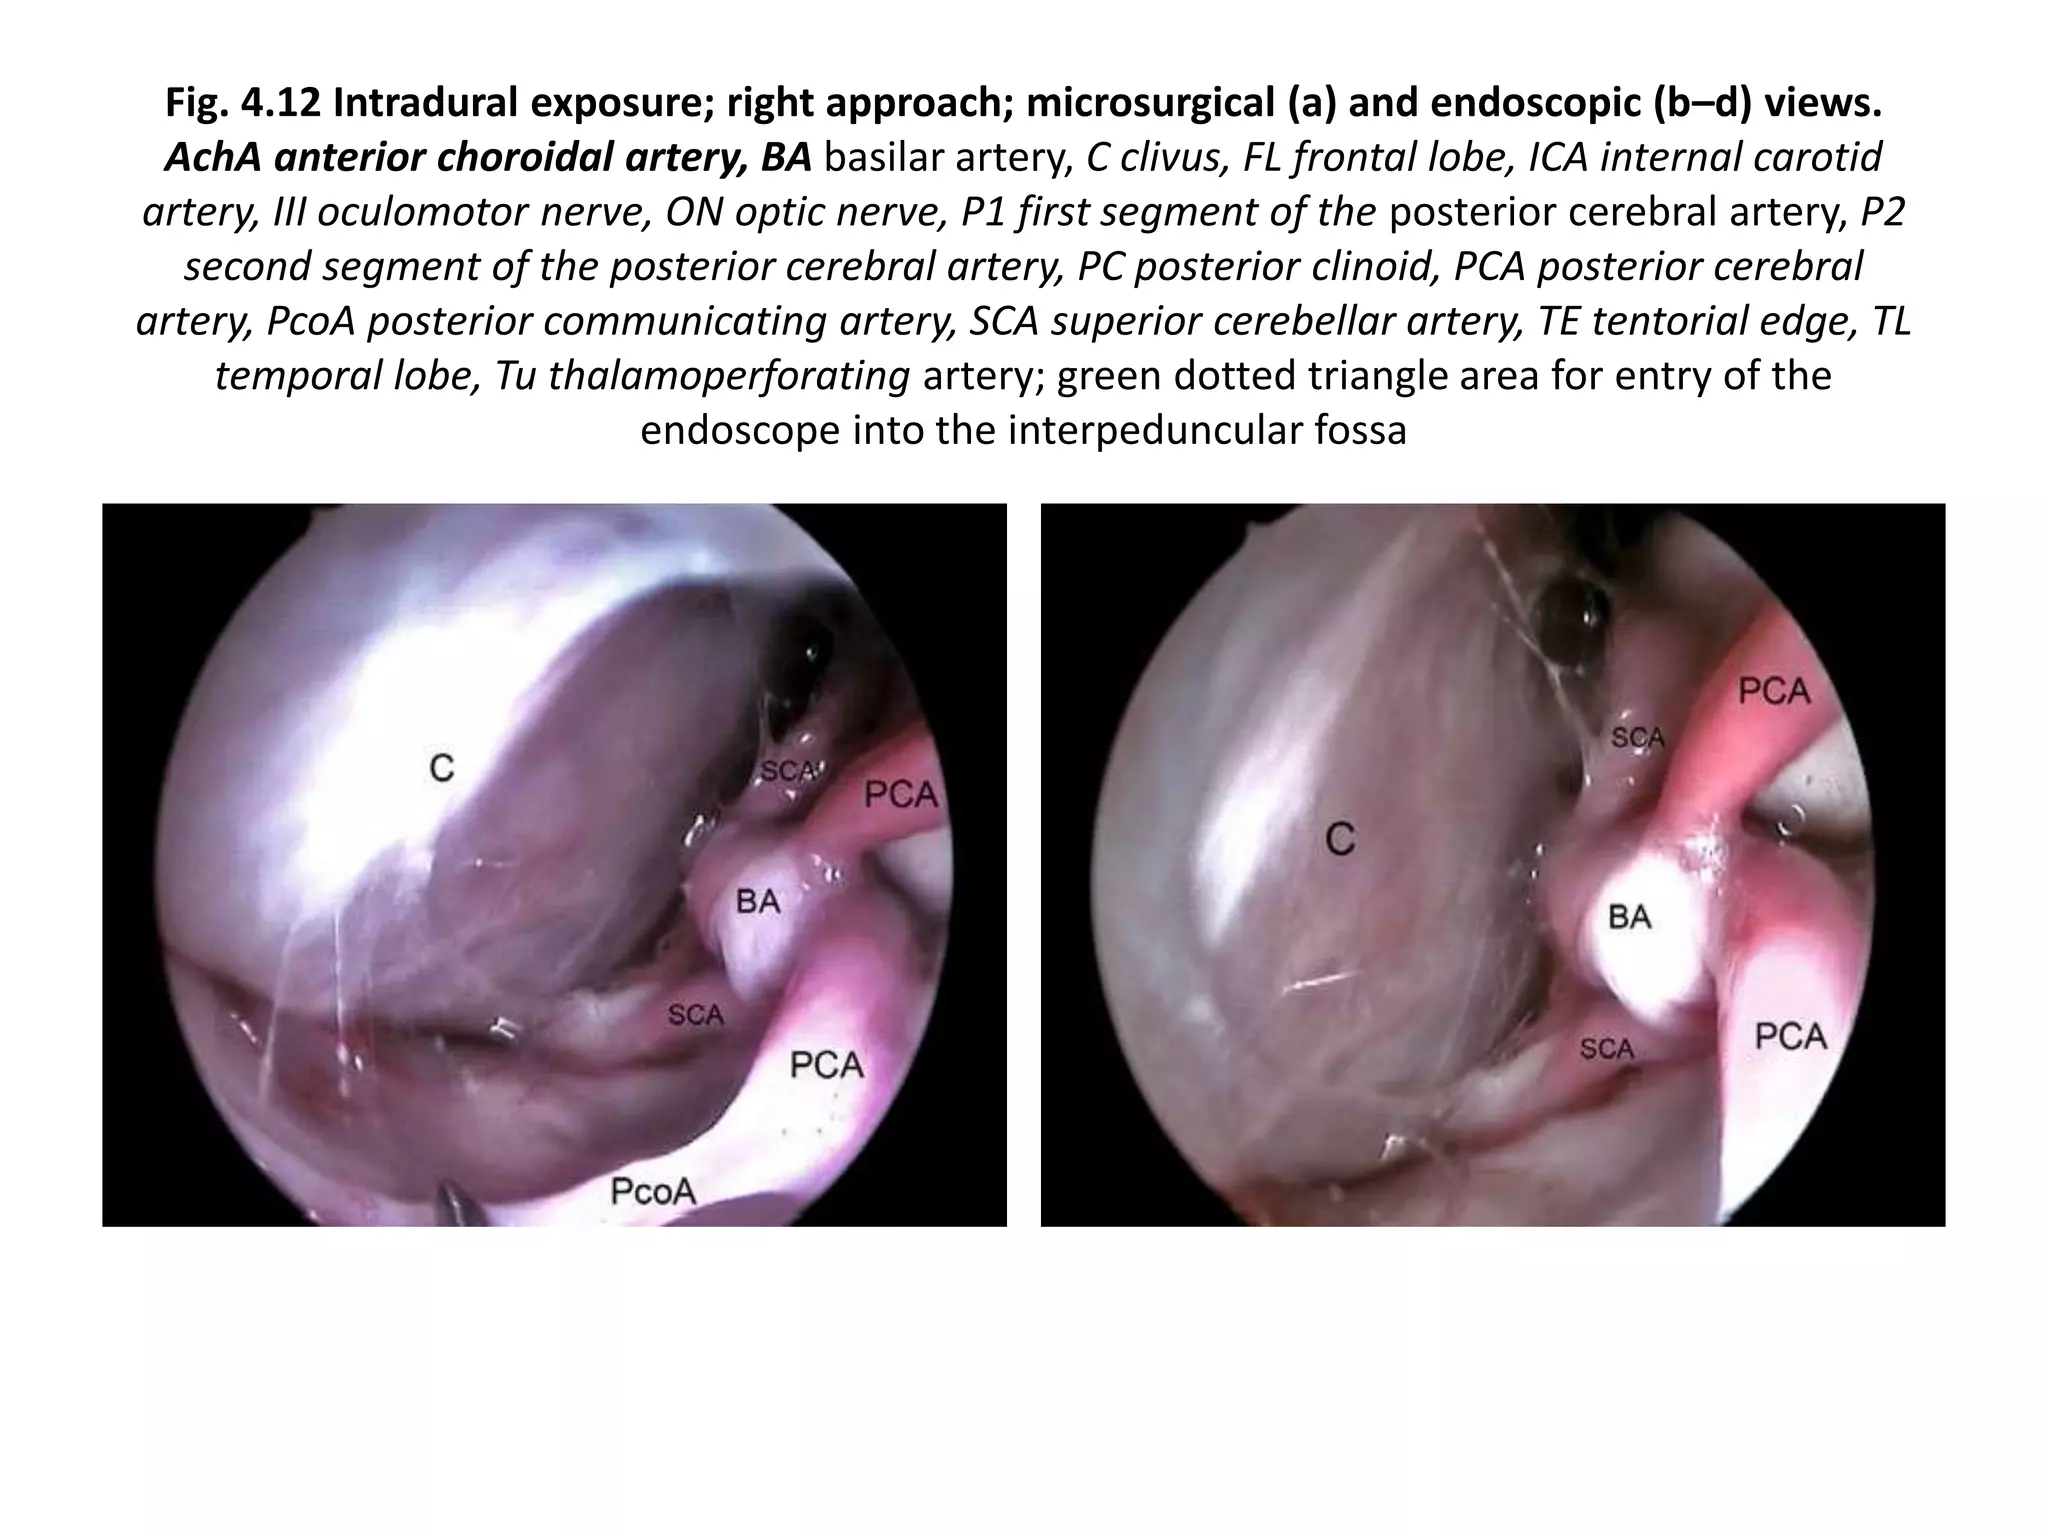

Endoscope-assisted microsurgery [ 45° endoscope in a corridor

between the carotid artery and the oculomotor nerve ]-- Fig. 4.12

Intradural exposure; right approach; microsurgical (a) and endoscopic (b–d) views. AchA

anterior choroidal artery, BA basilar artery, C clivus, FL frontal lobe, ICA internal carotid artery, III

oculomotor nerve, ON optic nerve, P1 first segment of the posterior cerebral artery, P2 second

segment of the posterior cerebral artery, PC posterior clinoid, PCA posterior cerebral artery, PcoA

posterior communicating artery, SCA superior cerebellar artery, TE tentorial edge, TL temporal

lobe, Tu thalamoperforating artery; green dotted triangle area for entry of

the endoscope into the interpeduncular fossa

Fig. 4.12 Intradural exposure; right approach; microsurgical (a) and endoscopic (b–d) views.

AchA anterior choroidal artery, BA basilar artery, C clivus, FL frontal lobe, ICA internal carotid

artery, III oculomotor nerve, ON optic nerve, P1 first segment of the posterior cerebral artery, P2

second segment of the posterior cerebral artery, PC posterior clinoid, PCA posterior cerebral

artery, PcoA posterior communicating artery, SCA superior cerebellar artery, TE tentorial edge, TL

temporal lobe, Tu thalamoperforating artery; green dotted triangle area for entry of the

endoscope into the interpeduncular fossa